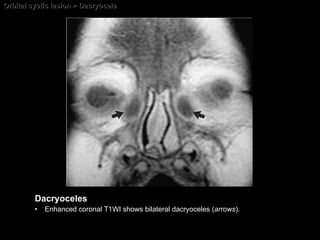

Dacryocele Lachrymal sac mucocele A cystic expansion of the  nasolacrimal sac .  Caused by a proximal or distal block of the nasolacrimal duct.  Dacryoceles are considered a congenital anomaly of the lacrimal drainage system. Usually apparent in the first few days of life.

Dacryocele Imaging findings; well-circumscribed, rounded lesions centered in the nasolacrimal sac region. Nonenhancing mass, unless infected. CT Nonenhancing (unless infected) low-density mass. MRI Hypointense on T1WI and hyperintense on T2WI.

Orbital cystic lesion > Dacryocele Dacryoceles Enhanced coronal T1WI shows bilateral dacryoceles ( arrows ).